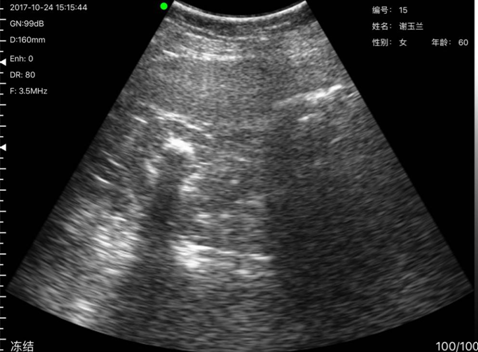

病例2姓名:刘x兰,性别:女,年龄:60岁,到我所就诊多次,但一直无法确诊具体何原因引起,但老人又特别能忍,未到大医院检测,本次发现其肾有大量亮点,疑似有结石,其到沙县医院复诊后确诊为肾结石,确诊报告与掌上B超机检测结果一致。